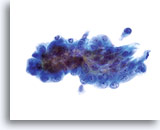

Kernen zijn vergroot, nemen vaak meer dan 2/3 van het cytoplasma in beslag en blijven doorgaans rond tot ovaal, met golvende celkernmembranen.

60x